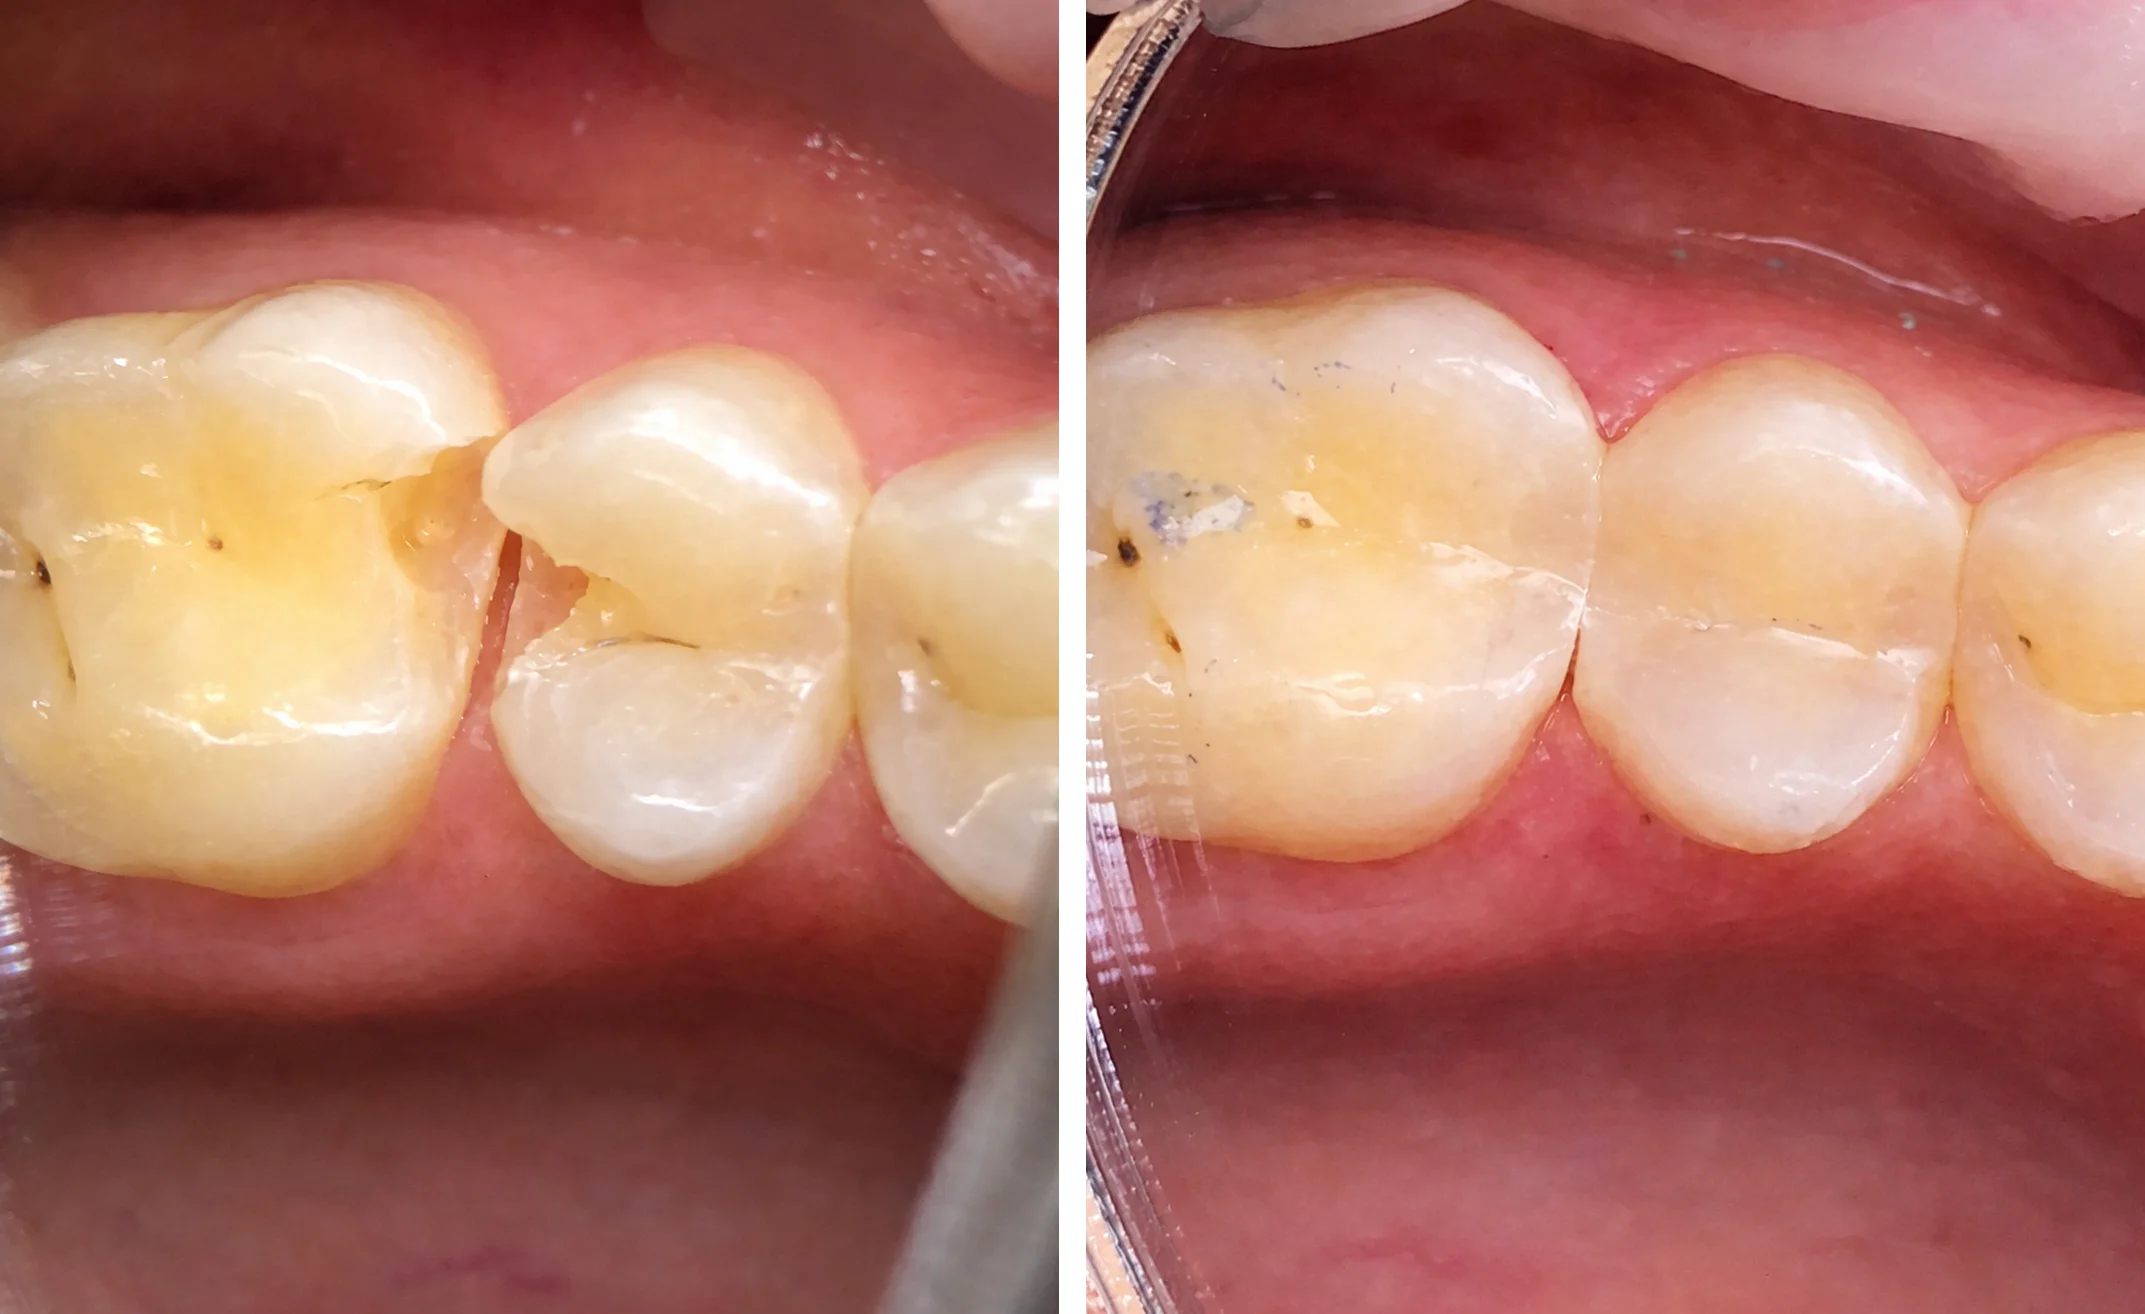

Фотополімерна пломба — підходить, коли уражено до 40% зуба, виглядає природно, служить 5–10 років.

Керамічна вкладка — використовується, коли зруйновано понад 50% зуба. Вона міцніша, довговічніша (10–15 років), точно відтворює анатомію та витримує високе жувальне навантаження.